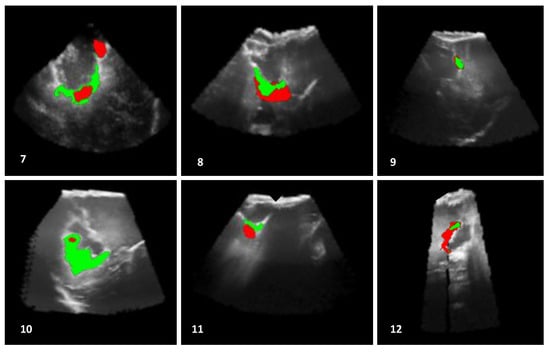

The outcomes, obtained by the automatic proposed method, are presented in Figure 7, Figure 8 and Figure 9. In addition, the algorithm results (in green) and the ground truths (in red) are overlaid on a selected slice of the 3D iB-mode images for visualization purposes. Table 2 summarizes the qualitative and quantitative evaluation. The former is based on expert observations, and the latter is performed by using the overlap, accuracy, area under the curve and error rate measures. The experiments showed that our approach succeeded in detecting the position of all tumor remnant areas in 15 out of 19 patients (). For these cases, a qualitative coding of 1/−1 (all tumorous regions were detected) or 1/1 (all tumorous regions were detected and extra suspected regions, as well) was observed. Regarding the four unsuccessful cases, the areas with tumorous tissue were partially detected in two patients (Patients 2 and 7, where ), and the algorithm failed in the two other cases (Patients 14 and 18, where ). One failure reason is the position of tumor residuals near the image top (Patients 7 and 18). These areas are removed in the preprocessing steps to eliminate artifacts caused by the US probe. The method was also tested on patient data from the set B where false positives were detected in the cases of Patients 20 and 23 and none for Patients 21 and 22.

Figure 8.

Results of residual tumor identification from Patients 7 to 12. The results obtained by using the proposed automatic method (in green) are superimposed with the expert manual segmentation (in red). The algorithm missed the detection of other tumorous structures in the case of Patient 7, and it identified a large region in the case of Patient 10.